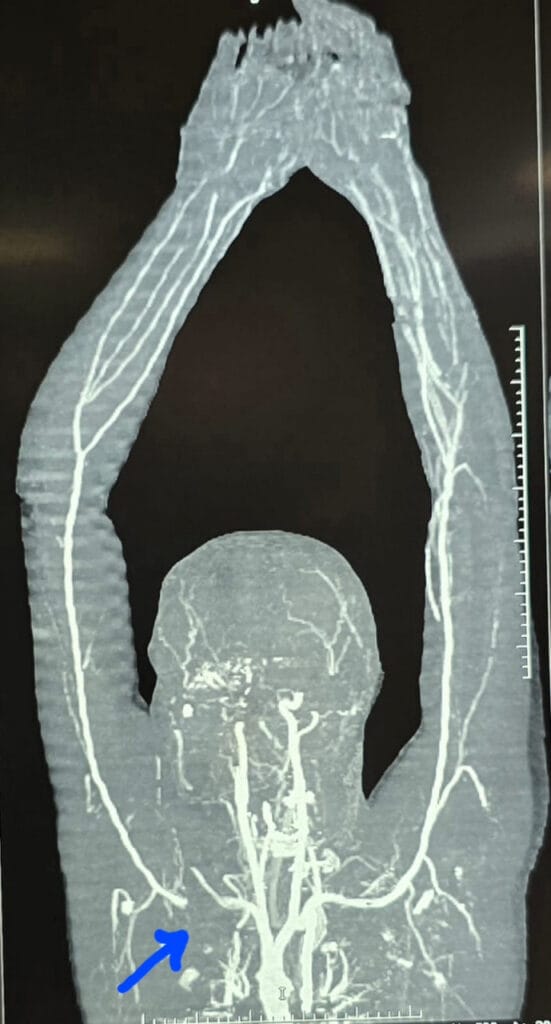

After cutting the collarbone, it was found that the artery was completely damaged for approximately 3 cm. A 7×30 mm Dacron graft (artificial vein) was inserted to repair it. Approximately 5 units of blood were transfused during the surgery, and after approximately 4 hours of painstaking work, blood flow to the arm was restored. The brachial plexus (nerve system) was completely protected, as damage to it can lead to permanent paralysis. After the operation, the collarbone was reattached with a plate.